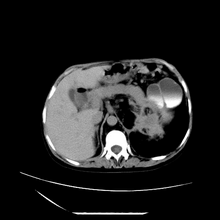

女性,41岁,发现左腹部包块3年,现行ct检查,检查前做过静脉肾盂造影。

左侧低密度区是脂肪密度,中间可见条索状软组织样密度影,现主要想知道左肾前下缘圆形软组织样密度影,内见低密度水样密度影,这是什么?

脾脏增大,左肾后方脂肪增多,脊柱前方脂肪增多,左肾窦脂肪增多,左肾变形,双肾积水以左侧为著,左肾内侧及上方见环形软组织肿物影,内部低密度区,考虑1盆腹腔/腹膜后及左肾窦脂肪增多症2左肾内侧病灶可能为左肾上腺病灶,可能为脂肪增多的原凶

1)考虑左肾替代性脂肪瘤病;不排除左肾错构瘤。2)双肾积水。

肾窦脂肪瘤病及肾替代性脂肪瘤病被认为是脂肪增殖程度不同的一种疾病。正常情况下肾窦内有少量脂肪组织充填,在某种情况下肾实质会发生萎缩,而以肾窦、肾门为中心脂肪或(和)纤维组织可出现增殖,当增殖局限在肾窦、肾门区时称为肾窦脂肪瘤,若同时部分或全部取代了萎缩破坏的肾实质时称为肾替代性脂肪瘤病。

发病机理有2种学说,大部分人认为是由于某些具有破坏性的肾脏疾病,如肾结石并感染、肾结核等造成肾破坏、萎缩,继发了大量的脂肪组织增殖;另一部分则认为肾脏慢性炎症可刺激脂肪组织的增殖,肾萎缩是继发的。

ct典型表现为以肾窦肾门为中心大量弥漫性脂肪积聚,鹿角状结石及萎缩的肾实质。合并肾周感染时,肾轮廓不清,周围有粘连性改变。

诊断rsl的必备条件是肾窦、肾门的脂肪组织增生和肾实质的萎缩,而且本例因为ivp后扫描不好判断有无肾结石但可能性较小;另外,占位效应显著,脾后缘都受压了,肾门以下肾实质残缺,支持肾脏错构瘤.